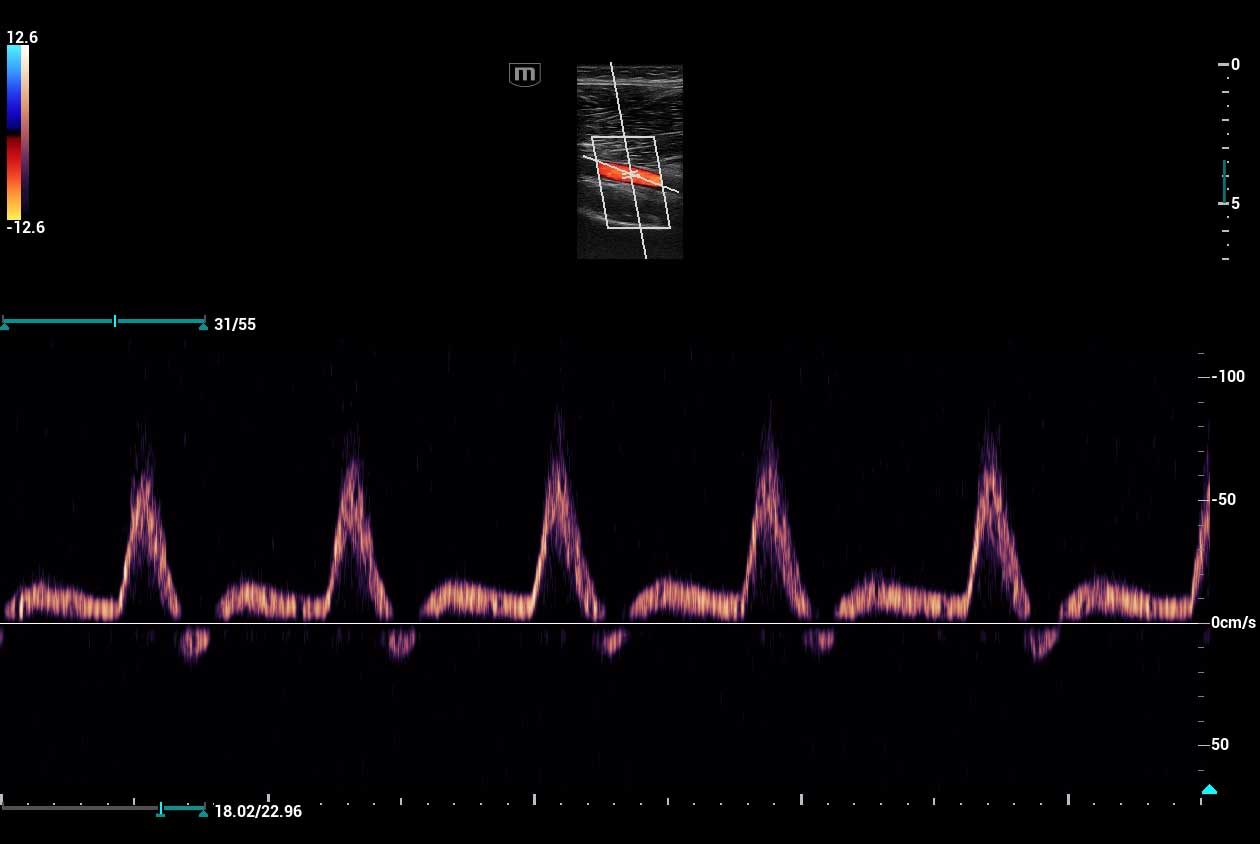

Clinical Images